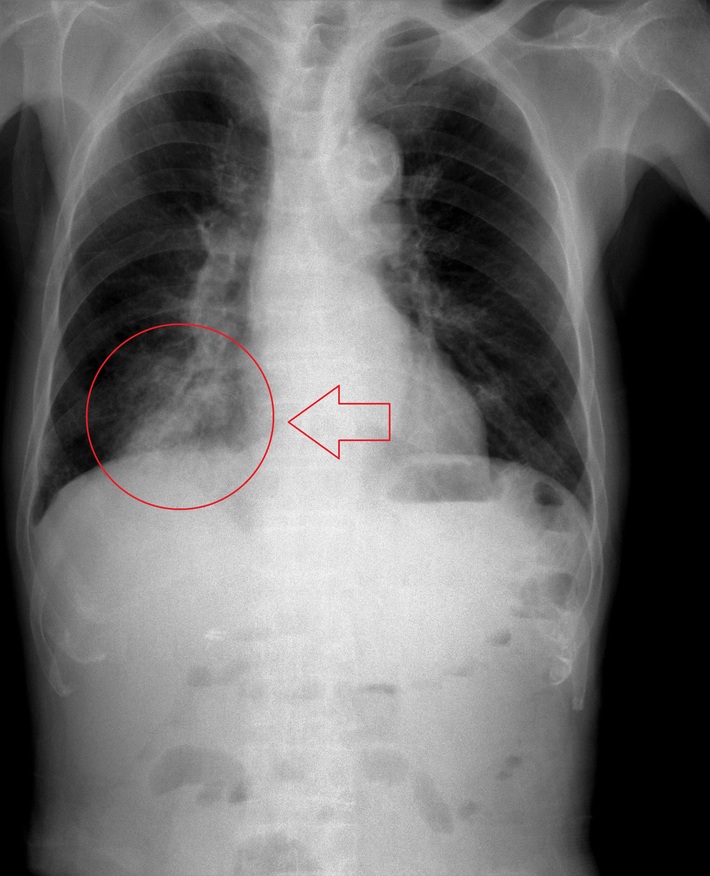

Ella Kazerooni, MD, a radiologist at the University of Michigan Medical Center, believes that we can’t rely on AI to determine the difference between COVID-19 and other respiratory illnesses. “I’ve looked at the work around AI and COVID, and I’m not a big fan,” she told STATNews. “When you’re just comparing normal and abnormal scans and nothing in between. It’s not very helpful.” The American College of Radiology and the Radiological Society of North America agree that medical imaging shouldn’t be prioritized in testing for the virus, arguing that the infection can be contracted through equipment use.

Yet, some high tech medical imaging companies are trying to prove naysayers wrong. RADLogics, a developer of an algorithm that analyzes CT images to detect coronavirus and also “scores” the progression of the infection, claims that their program has been used on hundreds of cases in 10 hospitals throughout China and Russia. According to STATNews, they have applied for emergency authorization from the Food and Drug Administration to use the software in the U.S.